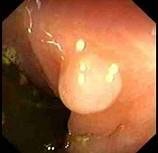

男性,46岁,有结肠癌家族史,行肠镜检查如图,诊断为 ( )A.直肠癌B.直肠炎性息肉C.直肠腺瘤样息肉D.直肠绒毛样息肉E.克罗恩病

问题 男性,46岁,有结肠癌家族史,行肠镜检查如图,诊断为 ( )

选项 A.直肠癌 B.直肠炎性息肉 C.直肠腺瘤样息肉 D.直肠绒毛样息肉 E.克罗恩病

答案 B